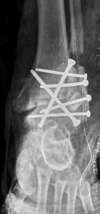

Arthrose de cheville post traumatique (séquelle d'entorses à répétition), traitée par blocage articulaire (arthrodèse)